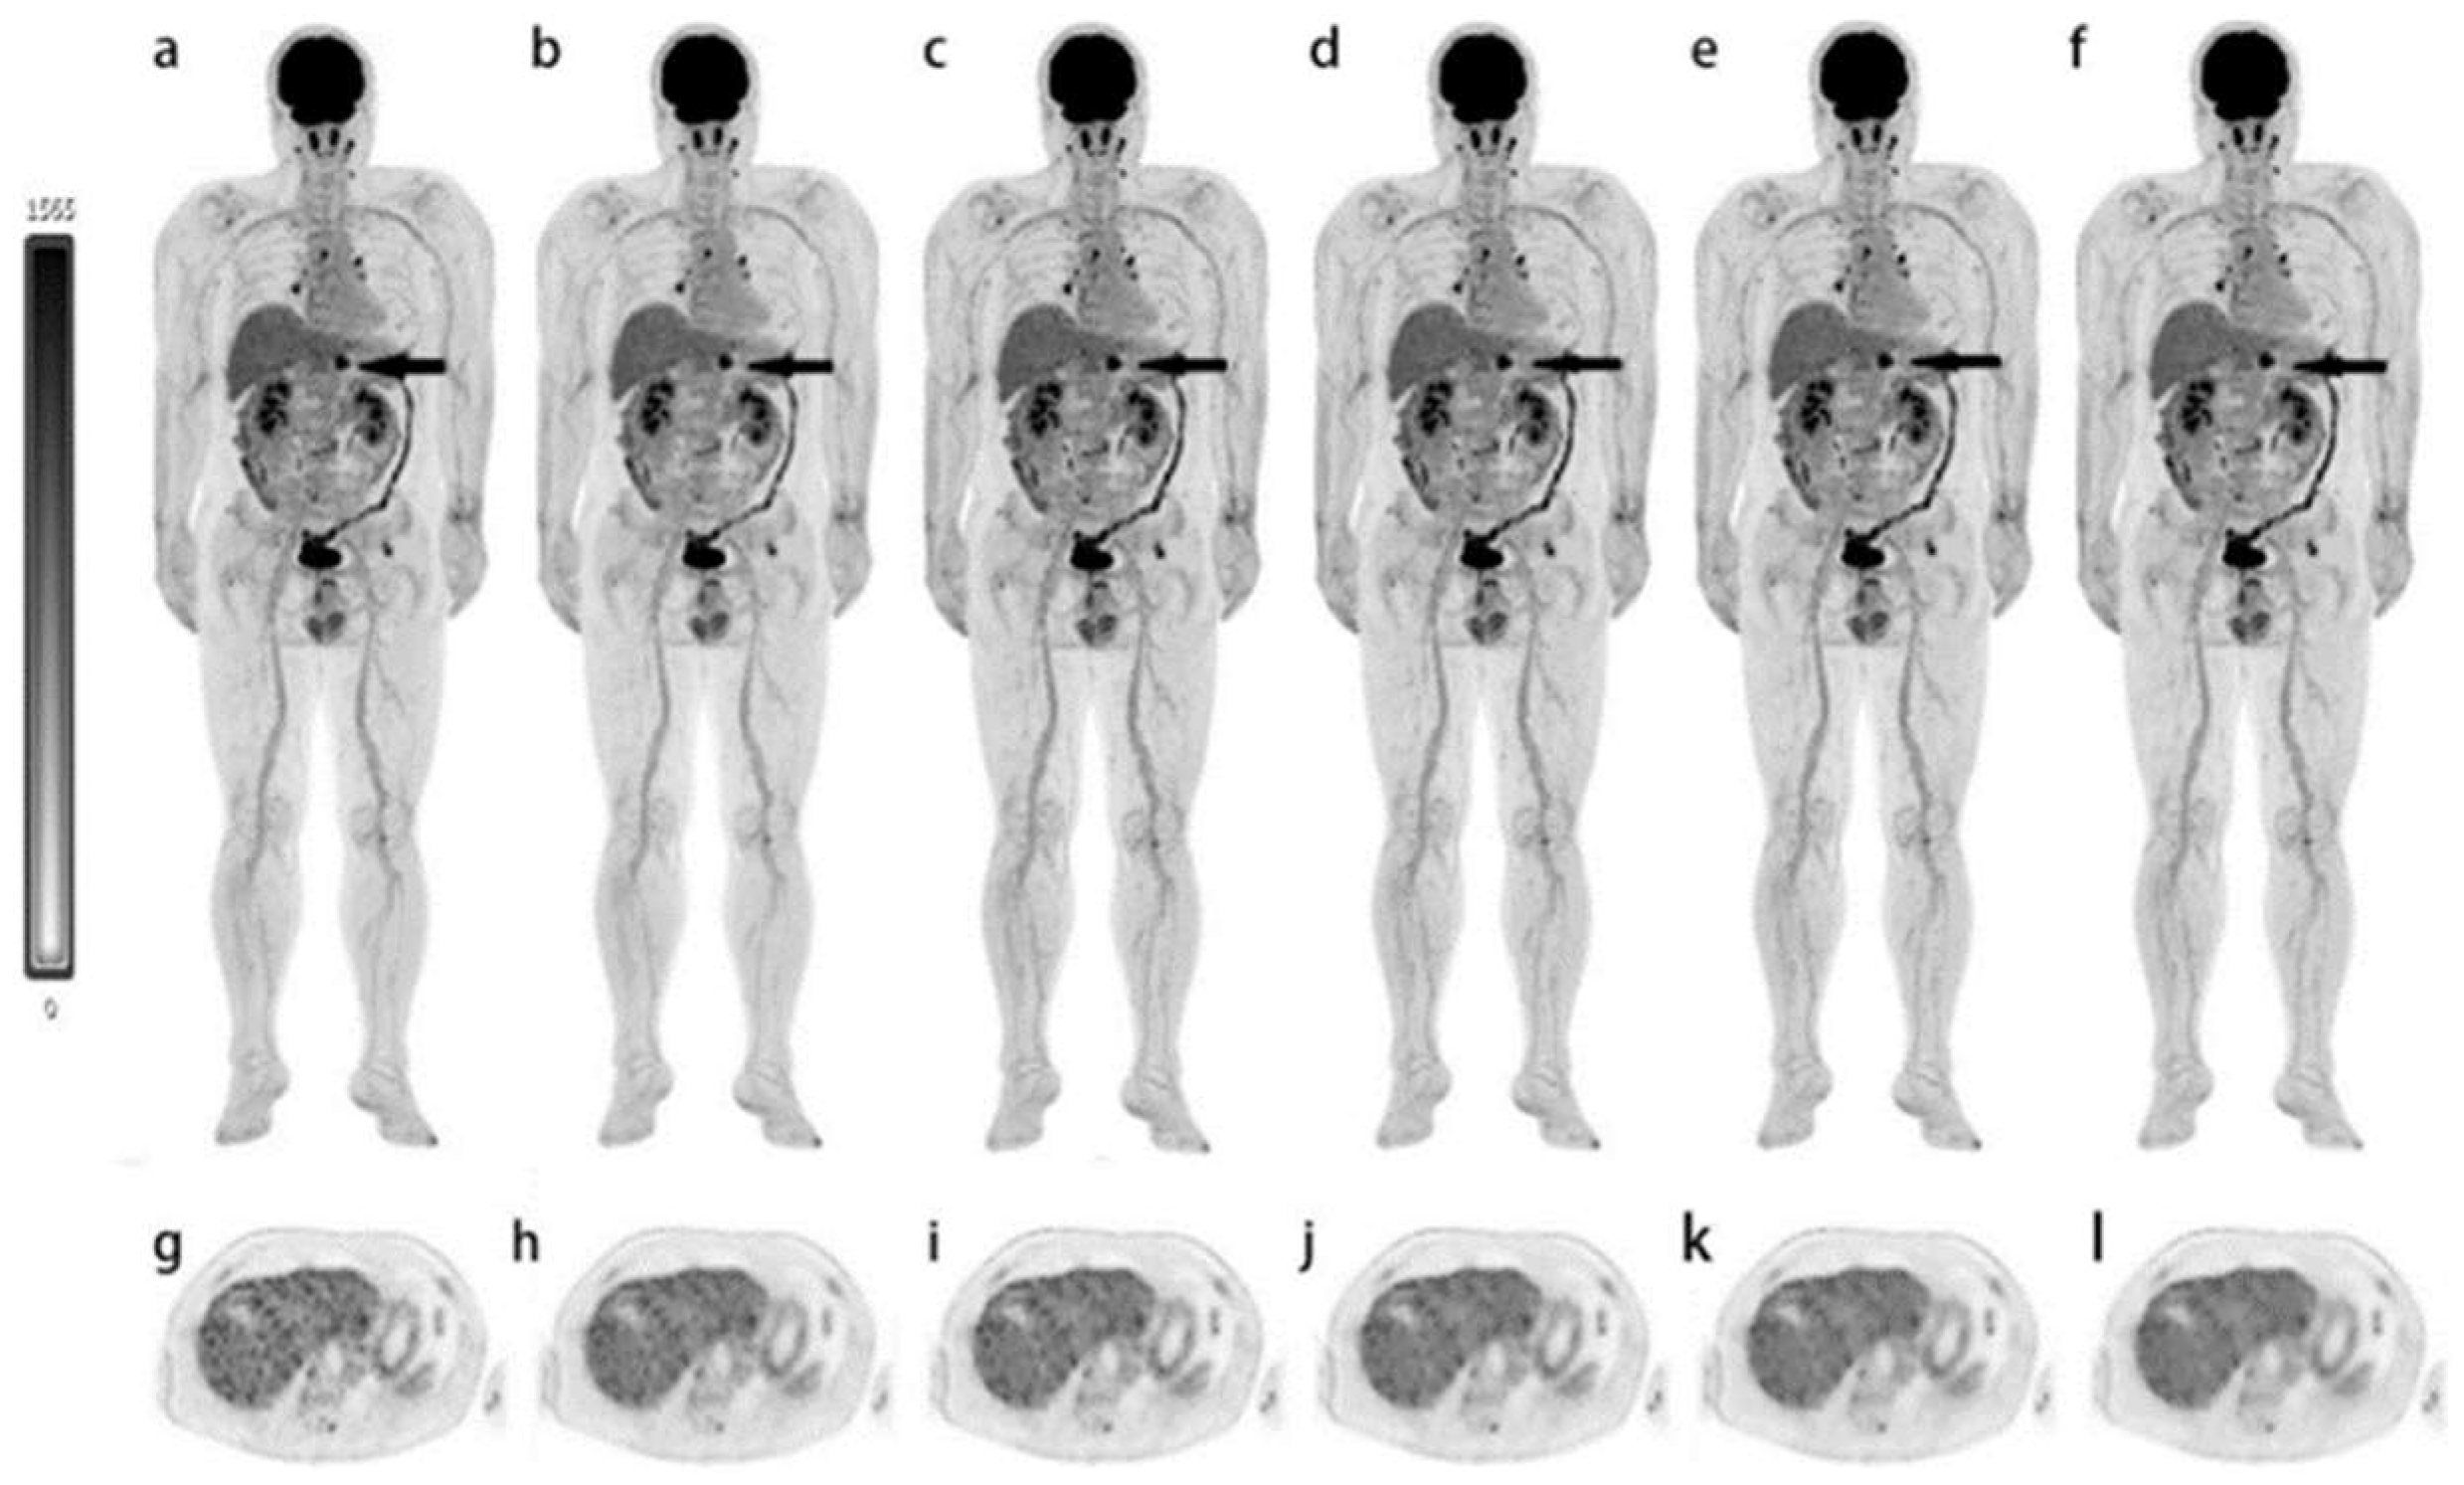

- Alberts, I.; Hunermund, J.N.; Prenosil, G.; Mingels, C.; Bohn, K.P.; Viscione, M.; Sari, H.; Vollnberg, B.; Shi, K.; Afshar-Oromieh, A.; et al. Clinical performance of long axial field of view PET/CT: A head-to-head intra-individual comparison of the Biograph Vision Quadra with the Biograph Vision PET/CT. Eur. J. Nucl. Med. Mol. Imaging 2021, 48, 2395–2404. [Google Scholar] [CrossRef]